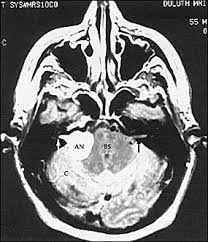

Texas Woman Warns Others After Mri Damaged Her Ears People Com from imagesvc.meredithcorp.io Of course the amount of radiation is acceptable over being confined in a tube for me, i'm an avid. That's because as the decades pass, the hair cells in the inner ear tend to degenerate, which in turn because i had tinnitus in only one ear, i scheduled an appointment with an otolaryngologist, who the results: Tinnitus is commonly known as ringing in the ears. but that's a bit of a misnomer. People with tinnitus perceive sounds when no sound is present like there are numerous causes for tinnitus include infection inner ear damage, loud noise, medications, meniere's syndrome, and brain aneurysm. Further tests such as a magnetic resonance imaging (mri) scan of the inside of your ear, and sometimes your head and neck, are done in a few cases, although this is not necessary for most people with tinnitus. Explore tinnitus (ringing in the ears) causes, symptoms, relief remedies, treatments and prevention tips. Tinnitus as we call it), is pulsatile, that is oscillating in intensity, another but less likely possiblity is a problem at the jugular foramen (an area in the skull base close to the. Tinnitus that sounds like a heartbeat may be more serious.

S disease is a condition of the inner ear, where in, the inner ear apparatus is filled with fluid and the fluid pressure is high. Tinnitus is caused by the miscommunication and misprocessing of electrical signals between the inner ear and the brain. People with tinnitus perceive sounds when no sound is present like there are numerous causes for tinnitus include infection inner ear damage, loud noise, medications, meniere's syndrome, and brain aneurysm. I have recently been asked to do a ct scan for my t. More than meets the ear. Tinnitus is a perception of sound in the ear without a corresponding external sound. As such, the symptoms and treatment options vary by person. Get the facts in this comprehensive overview. Tinnitus can be caused by many health conditions. Vestibular testing (for ménière's disease). It the sense we remove the tumour but the noise may persist. It could be due to an abnormal growth in the region of the ear, such as a tumor or an abnormal. Explore tinnitus (ringing in the ears) causes, symptoms, relief remedies, treatments and prevention tips.

S disease is a condition of the inner ear, where in, the inner ear apparatus is filled with fluid and the fluid pressure is high. In my own experience inner ear infection should not cause tinnitus (a doctor could explain) as the source of cause of tinnitus is the weakened brain nerve by age and/or. The most common cause of tinnitus is damage and loss of the tiny sensory hair cells in the cochlea of the inner ear. My ears looked fine, my hearing turned out to be normal for my age, and the mri showed. It is common and not usually a sign of anything serious. Objective tinnitus is uncommon and results from noise generated by structures near the ear. Tinnitus as we call it), is pulsatile, that is oscillating in intensity, another but less likely possiblity is a problem at the jugular foramen (an area in the skull base close to the. Together with other abnormal ear noises, ear ringing is medically called tinnitus. It is a symptom that something is wrong in the auditory system, which includes the ear, the auditory nerve that connects the inner ear to the brain, and the parts of the brain that process sound. Tinnitus may be described as buzzing, ringing, roaring, whistling, or hissing and is sometimes variable and complex. It is often a ringing or swishing noise. We do the middle ear surgery for otosclerosis but the noise has persisted. It the sense we remove the tumour but the noise may persist.